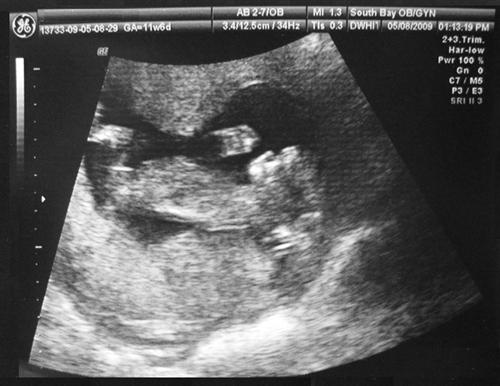

11 Weeks 6 Days Sono